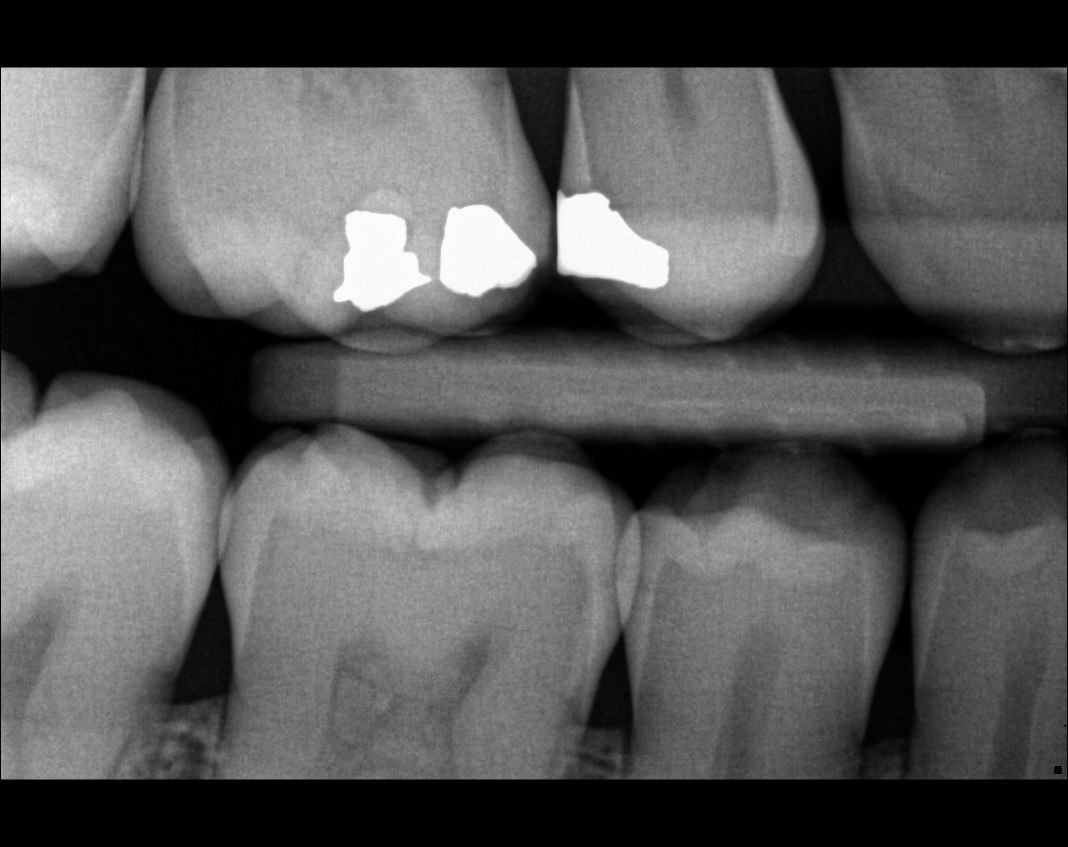

Question 7: What are the options associated with the distal surface of the tooth # 2.1 and mesial surface of the tooth # 2.2 respectively?

Question 8: What is the condition associated with the occlusal surface of the tooth # 1.6?

Question 9: What is the condition associated with the mesial and distal surfaces of the tooth # 1.4 respectively?

Question 10: What is the condition of the distal surfaces of the teeth # 1.5 and 1.6 respectively?

Quistion 11: What are the conditions of the distal and mesial surfaces of the tooth # 4.5 respectively?

Question 12: What option can describe the mesial surface of the tooth # 3.7?

Question 13: What option can describe the mesial surface of the tooth # 3.8?